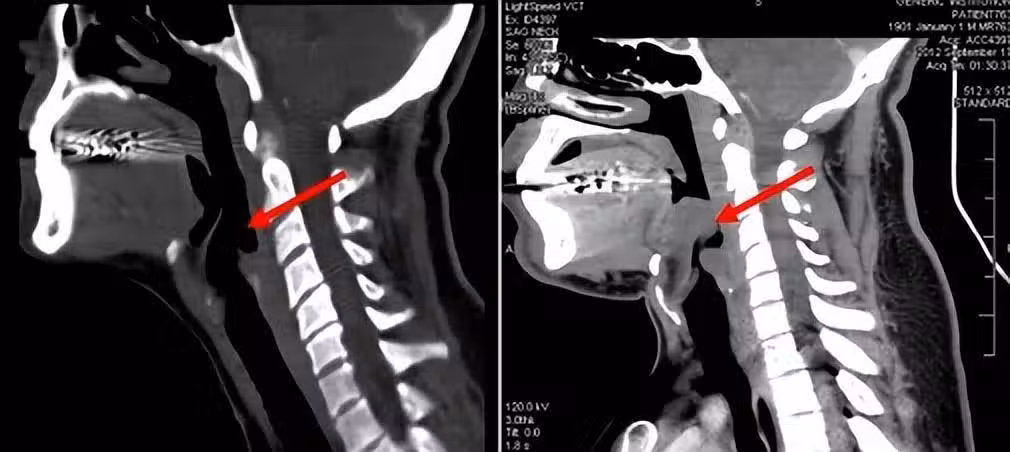

一般,急性會厭炎的病情進展十分迅速,一旦發病後沒有及時診療,可在極短時間內窒息,因此死亡率較高。

導致急性會厭炎的原因有很多。

第一個是感染,比如年老體弱或有喉外傷的人,就很容易受到細菌或病毒感染。過敏體質的人在過敏後,也可能出現會厭炎。

其次是外部創傷,如果喉嚨受到外力創傷,或吸入高熱飲品以及有害氣體時,會厭也會受到損害。異物刺入也可能引發急性會厭炎。